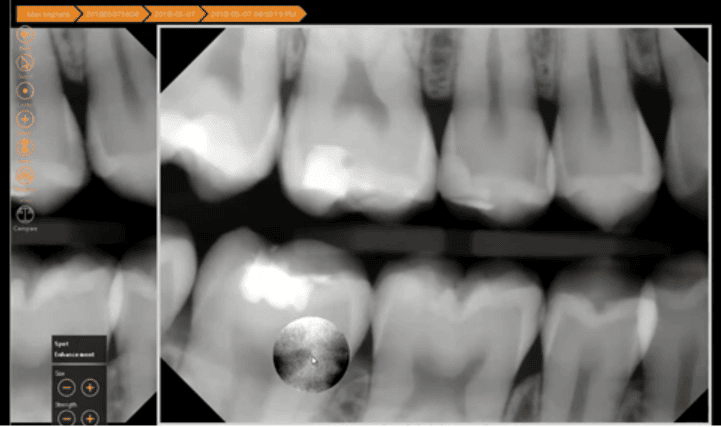

4. Taking a Closer Look with Spot Enhancements

Next, what if you’re happy with your exposure, but you want to take a closer look at a specific part of the radiograph? In Apteryx XVWeb, a spot enhancement tool allows you to visualize a particular area on a radiograph better. The spot enhancement tool will allow you to magnify any suspicious areas that require a closer inspection and view them with increased contrast. In this radiograph, the spot enhancement helps you take an enhanced look at one specific area.